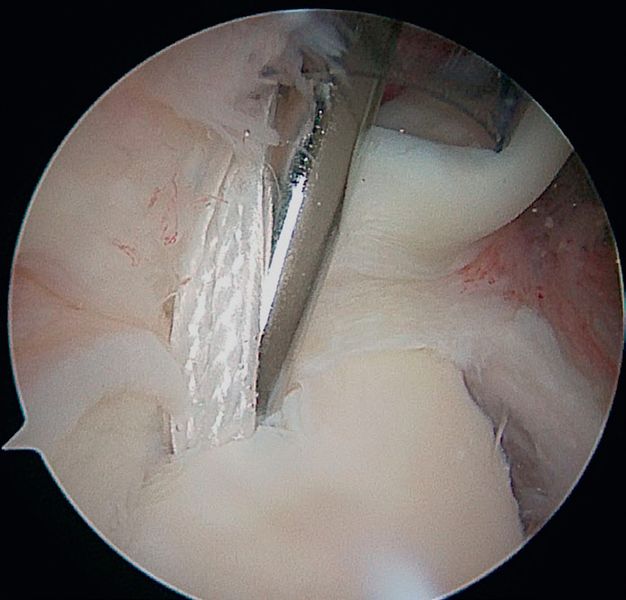

Arthroscopic SLAP II repair (right shoulder) using the posterior approach (soft point) and knotless anchors. f) Placing the anchor (knotless) to fix the tear backwards.